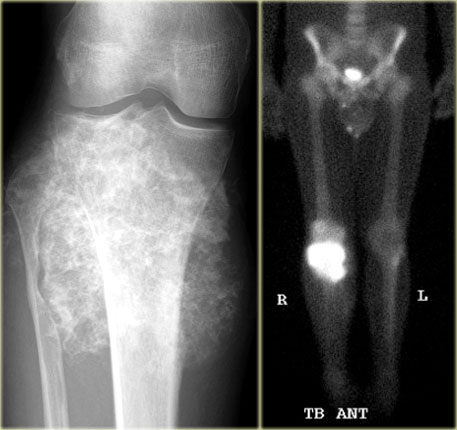

Chondroblastoma (9)

What are the findings:

• Well-defined osteolytic lesion in the talus.

• No matrix formation.

• Subtle reactive sclerosis.

• T2-WI with FS shows typical extensive peritumoral edema in the entire bone.

• High uptake on bone scintigraphy.

Diagnosis: Chondroblastoma.

The talar bone is one of the preferential sites for chondroblastoma.